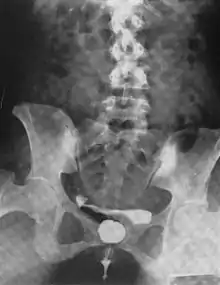

Another view of a urethral diverticulum seen on urethrogram

Urethral diverticulum is often an incidental finding.[2] It can be diagnosed using magnetic resonance imaging and/or micturating cystourethrography.[1] Other studies that can be used to diagnose urethral diverticulum include intravenous urography, urethroscopy, and/or ultrasound. Conditions that should be distinguished from urethral diverticulum in a differential diagnosis include overactive bladder, Gartner's duct cyst, Gartner's duct abscess, ectopic caeco-ureterocele, interstitial cystitis, pelvic inflammatory disease, endometriosis, and cancer.[3]